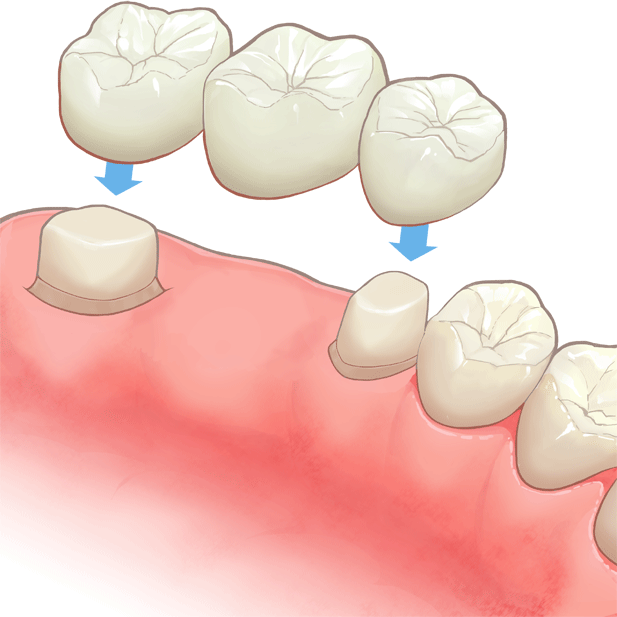

装着後